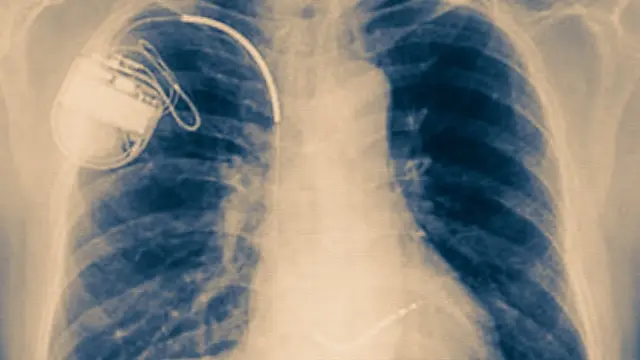

Fuente de la imagen, Thinkstock